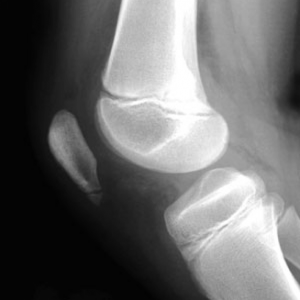

Sinding 2

In